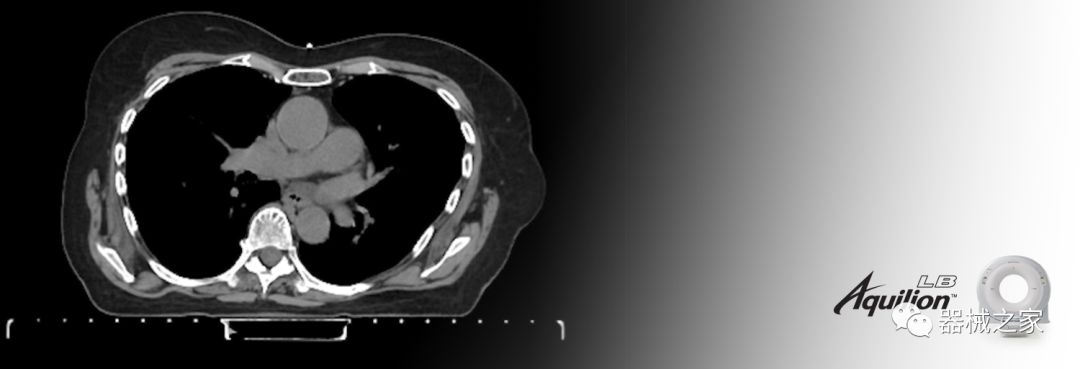

在以患者為中心的放射腫瘤學(xué)領(lǐng)域,計(jì)算機(jī)斷層掃描(CT)的可訪問(wèn)性,可重復(fù)性和靈活性至關(guān)重要。為了建立這些價(jià)值,佳能醫(yī)療系統(tǒng)美國(guó)公司現(xiàn)在正在擴(kuò)大其放射腫瘤學(xué)CT模擬產(chǎn)品,包括Aquilion Prime SP和Aquilion Lightning 80高級(jí)CT系統(tǒng)。除了Aquilion LB之外,Aquilion Prime SP和Aquilion Lightning 80現(xiàn)在還包括放射治療(RT)選項(xiàng),可為腫瘤學(xué)規(guī)劃提供高質(zhì)量的CT成像和精密工具。

擴(kuò)展視野(EFOV)可以看到更多的解剖結(jié)構(gòu)。Aquilion LB采用85 cm EFOV,而Aquilion Prime SP和Aquilion Lightning 70采用70 cm EFOV。

Aquilion LB專(zhuān)為滿足腫瘤學(xué)挑戰(zhàn)而設(shè)計(jì),同時(shí)優(yōu)先考慮患者護(hù)理。Aquilion LB的內(nèi)徑為90 cm,能夠幫助復(fù)雜的患者設(shè)置并提高患者的舒適度。CT模擬定位可以輕松鏡像放射治療定位,更加自信。該系統(tǒng)采用0.5 mm x 16排(32層)PUREViSION探測(cè)器技術(shù),70 cm視野,AIDR 3D和SEMAR技術(shù)。